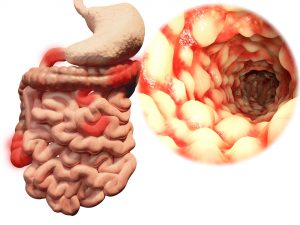

Crohn’s disease and ulcerative colitis progression and development have been found to be linked to “creeping fat.” Researcher Charalabos Pothoulakis said, “A well-appreciated feature of IBD [inflammatory bowel disease], especially longstanding Crohn’s disease, is intra-abdominal fat, also known as ‘creeping fat,’ which wraps around the intestine. However, it’s not clear whether this fat is protective or harmful. Our study offers insight into this phenomenon. We found that intra-abdominal fat cells may normally be programmed to dampen inflammation but, in fact, have acquired a tendency to promote inflammation in IBD.”

Crohn’s disease and ulcerative colitis progression and development have been found to be linked to “creeping fat.” Researcher Charalabos Pothoulakis said, “A well-appreciated feature of IBD [inflammatory bowel disease], especially longstanding Crohn’s disease, is intra-abdominal fat, also known as ‘creeping fat,’ which wraps around the intestine. However, it’s not clear whether this fat is protective or harmful. Our study offers insight into this phenomenon. We found that intra-abdominal fat cells may normally be programmed to dampen inflammation but, in fact, have acquired a tendency to promote inflammation in IBD.”

What is creeping fat?

Creeping fat is found in ulcerative colitis and Crohn’s disease patients, but it is still not well understood. More specifically, it has yet to be studied extensively, even though it has been known for decades.

Normal body fat is between 15 to 30 percent. In IBD sufferers, however, as much as 50 percent of the intestine is encased in creeping fat. Having more of this fat is associated with progression of Crohn’s disease.

The presence of creeping fat does not automatically classify a person as being overweight. In fact, many Crohn’s disease patients often have a healthy body mass index. Also, even though creeping fat is seen in Crohn’s disease, not all patients will develop it.